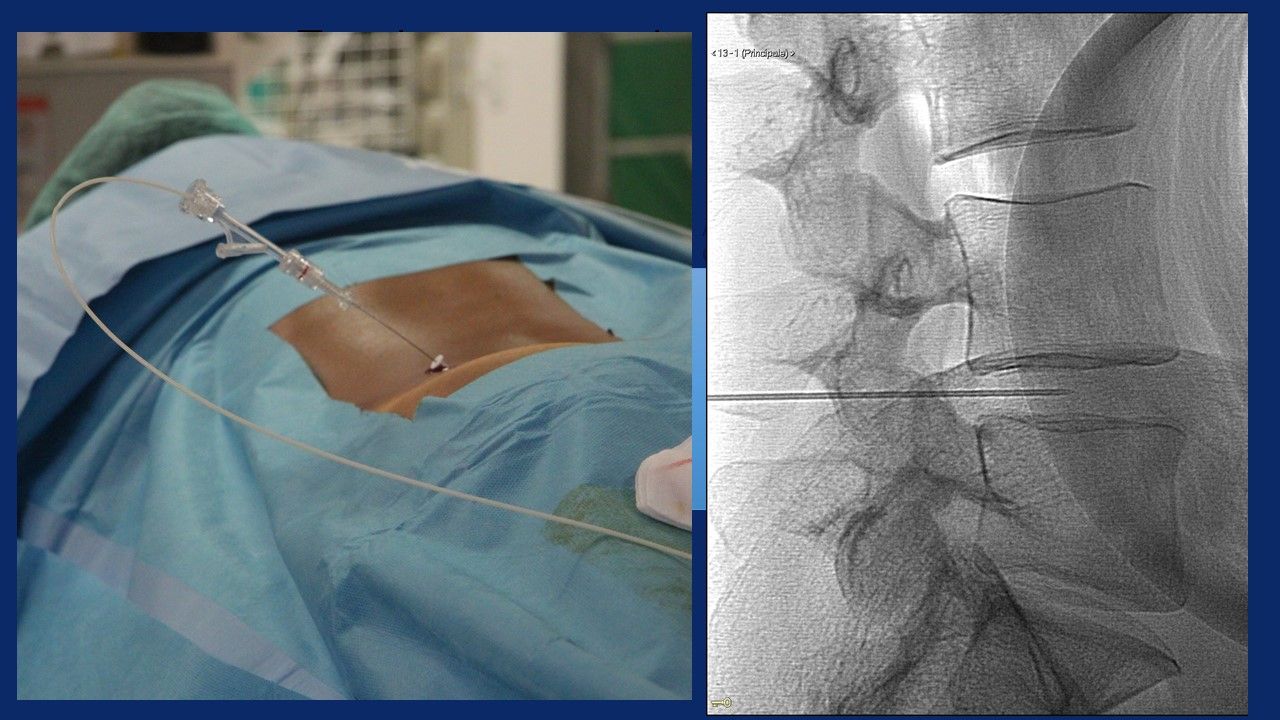

Ho maturato una notevole esperienza nella chirurgia mininvasiva percutanea del rachide, in particolar modo:

- nel trattamento della patologia discale mediante procedure di discectomia percutanea sotto guida fluoroscopica:

Nucleoplastica, Discectomia meccanica, Discectomia mediante laser, Discectomia Endoscopica, Discectomia mediante Discogel

- nel trattamento delle instabilità del rachide (spondilolistesi congenite o degenerative) mediante interventi di stabilizzazione mininvasiva percutanea con barre e viti , barre e viti cementate, tlif, plif, xlif, artrodesi delle faccette articolari.